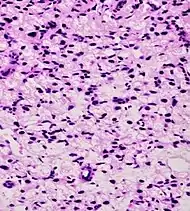

| Intraductal adenocarcinoma | 2.8%[10] | ![]() H&E and CK5/6 |

|||||

Intraductal carcinoma of the prostate with an infiltrative growth pattern may be morphologically difficult to distinguish from invasive cancer. One focus shows comedonecrosis (arrow), morphologically suggesting Gleason pattern 5 invasive carcinoma (a haematoxylin and eosin, b CK5/6)[19]

Intraductal carcinoma of the prostate with very patchy basal cells identified by immunohistochemistry. At least some of the glands lacking basal cell immunoreactivity represent intraductal rather than invasive carcinoma (a haematoxylin and eosin, b CK 5/6)[19]